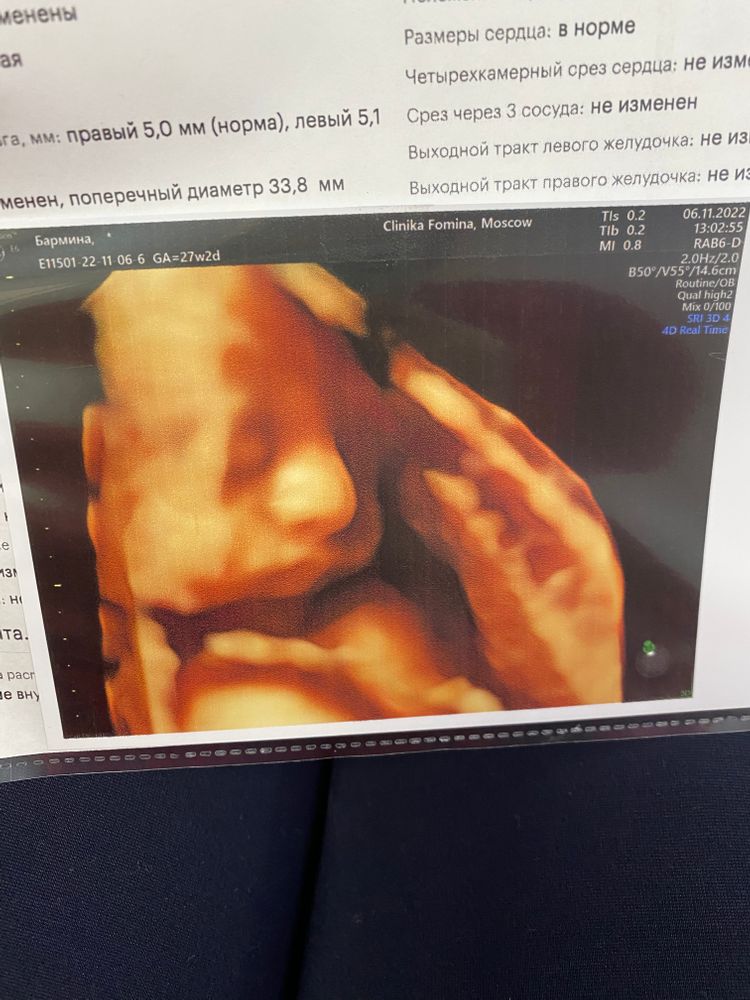

У меня похож)) Изображение Изображение

Изображение Изображение

Очень похож. Тут сыну 2 недельки Изображение

Один из двойни сильно похож, у второго фото смазанные получались всегда.  Изображение